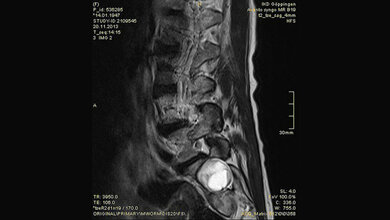

Oft wird die Erkrankung nur sehr spät entdeckt oder gar nicht: „Beschwerden werden als Bauchschmerzen abgetan oder auch als Rückenschmerzen, wenn die Aussackung der Hauptschlagader etwa auf die Wirbelsäule drückt. Kommt es dann zu einem Riss, im Fachbegriff ‚Ruptur‘, ist es häufig für einen rettenden Eingriff leider zu spät“, betont Prof. Schelzig. Pro Jahr werden in Deutschland über 17.000 Menschen gezählt, die an einem Aneurysma der Bauchschlagader operiert werden. Experten gehen aber davon aus, dass die Dunkelziffer noch höher ist, da nicht alle Fälle erkannt und damit auch nicht erfasst werden.

Das Screening erfolgt per Ultraschalluntersuchung. Wird dort festgestellt, dass die Bauchschlagader gefährlich erweitert ist, kann schnell gehandelt werden. Dabei kann etwa operativ ein Ersatzgefäß in den erkrankten Bereich der Schlagader eingenäht werden. Eine schonende Alternative dazu stellt das minimal-invasive Einbringen einer Stentprothese über einen kleinen Leistenschnitt dar. Hierbei wird die Gefäßprothese unter Röntgenkontrolle exakt an die erforderliche Stelle geschoben und dort entfaltet. Auf eine große Operation kann so verzichtet werden.